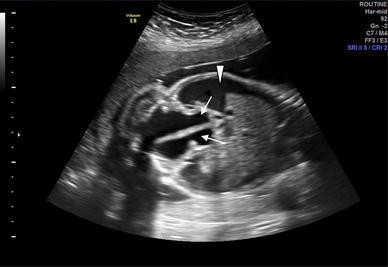

Sagittal view of the fetal pelvis and abdomen showing a septate cystic mass connected to two dilated uterine cavities (arrows) with the characteristic four-chamber appearance. Also note the presence of fetal ascites (arrowhead)